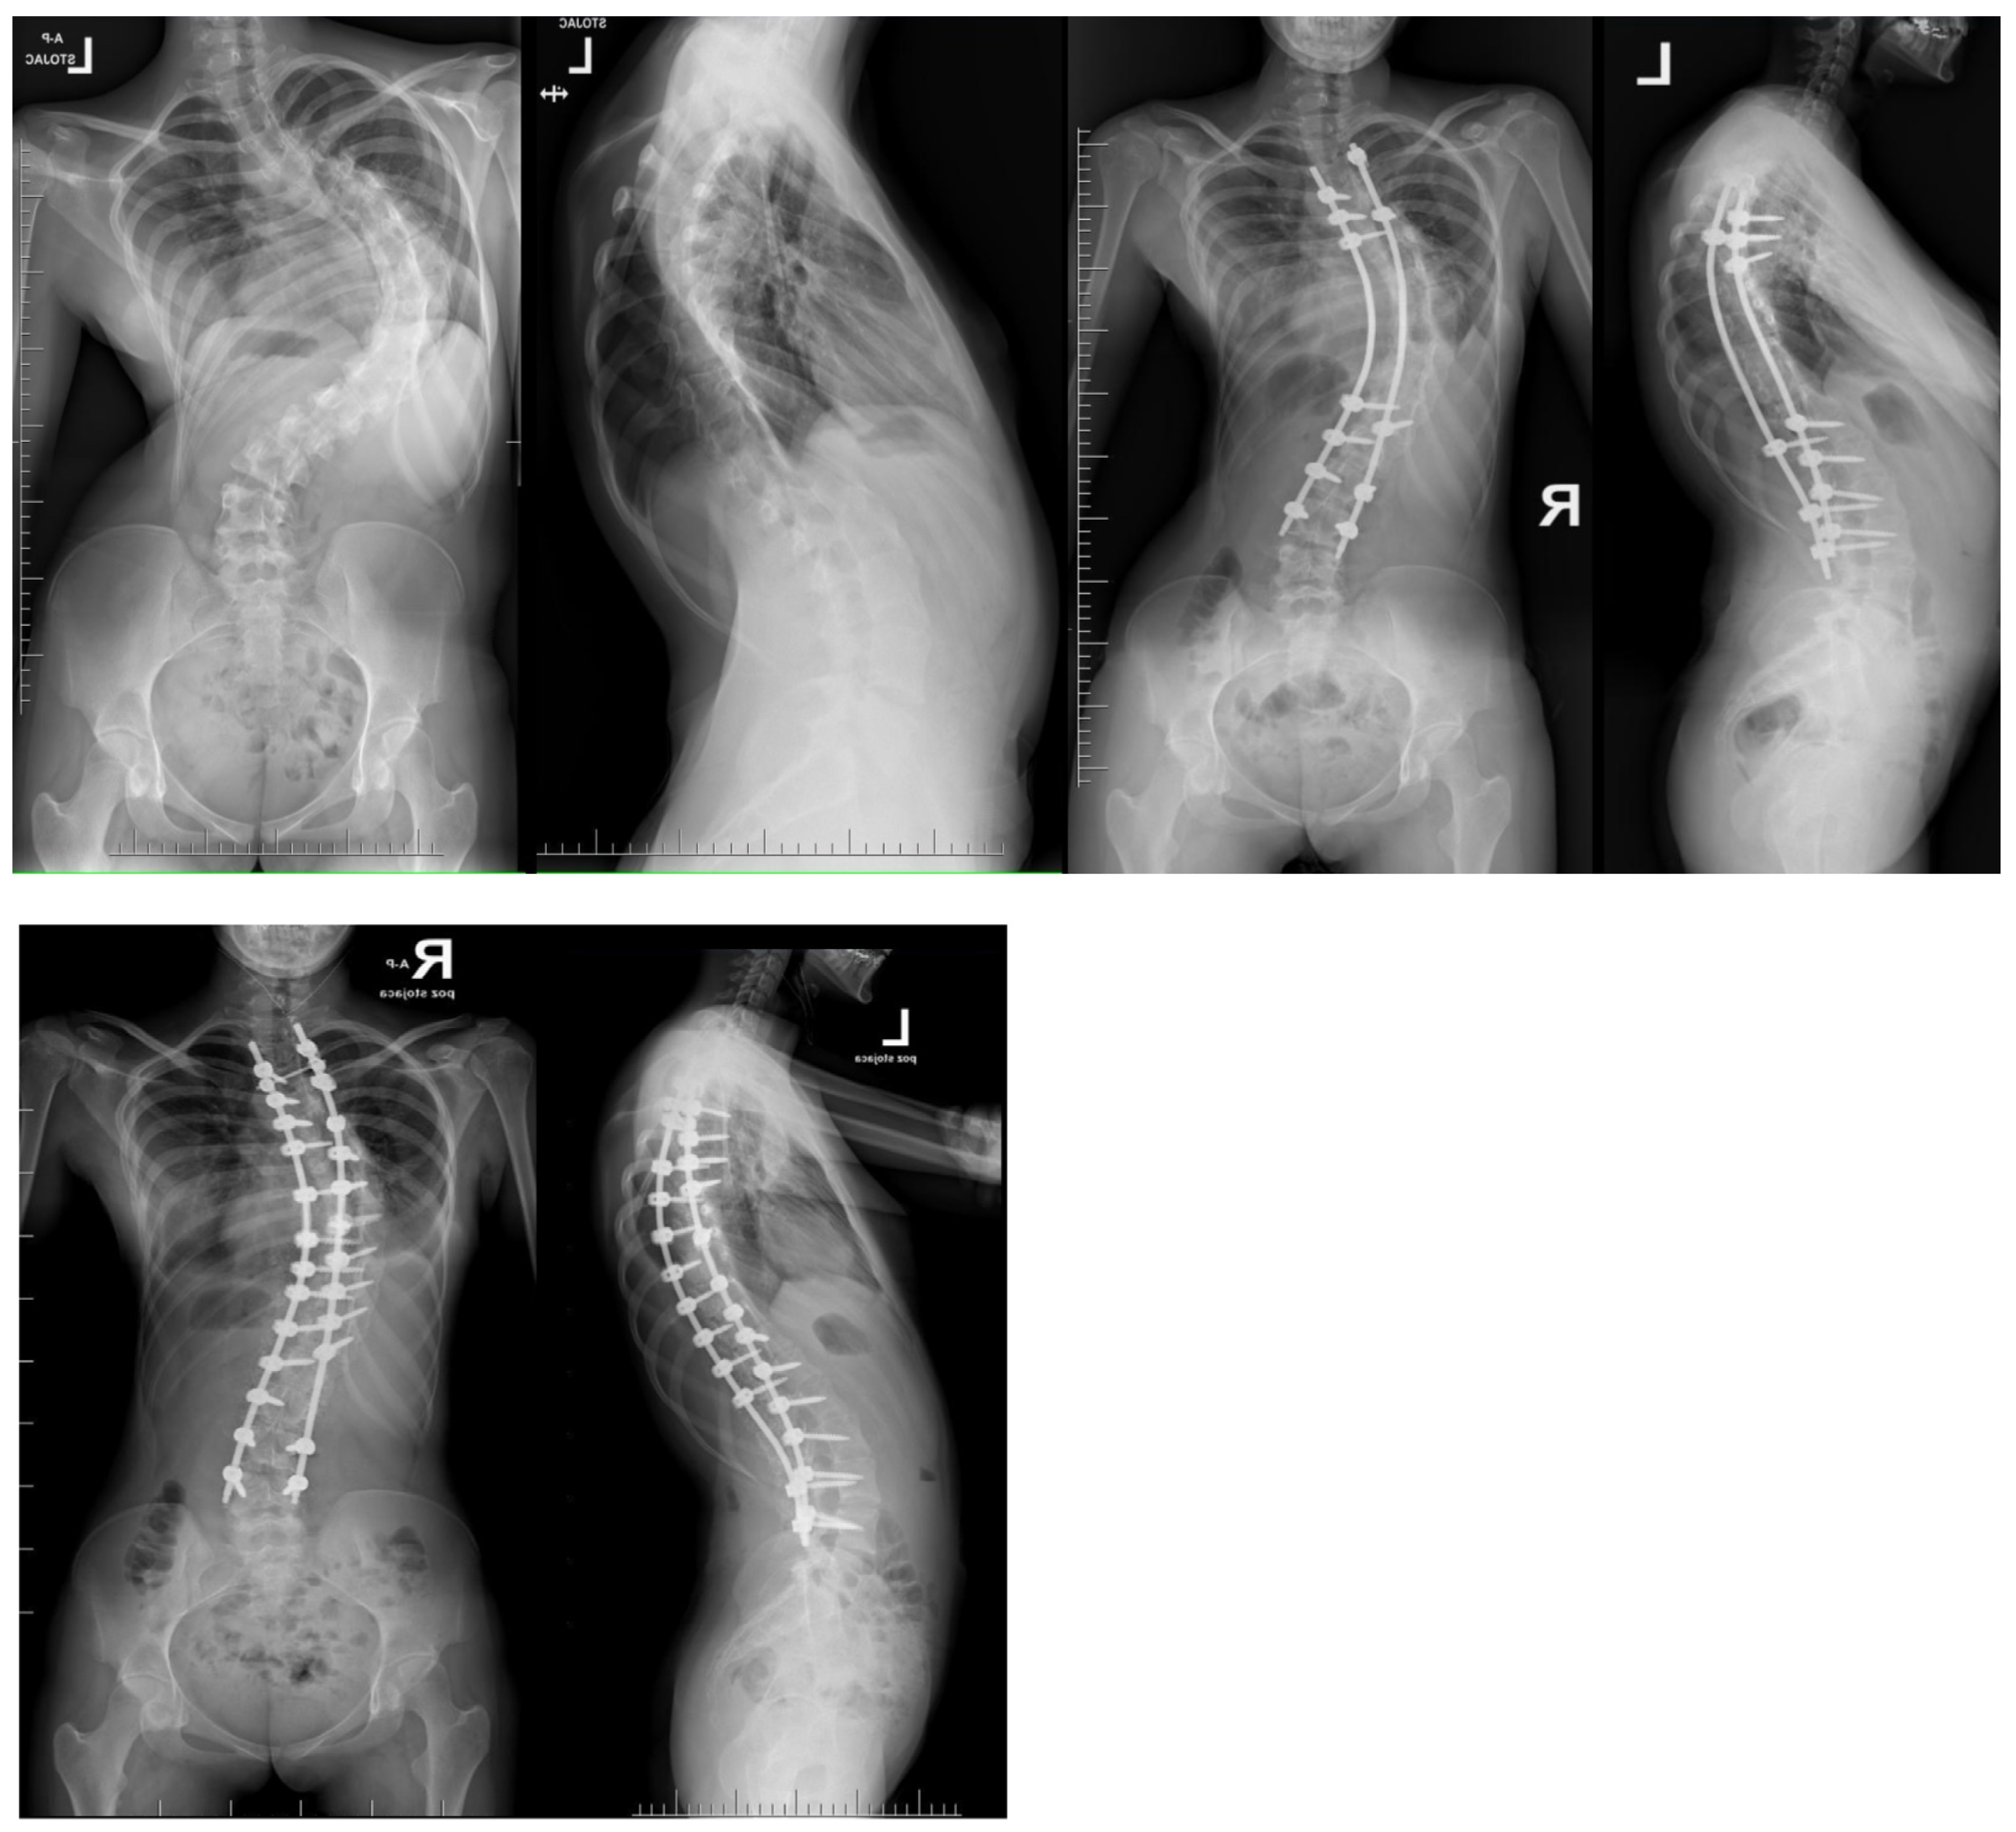

Figure 9.

Radiographs obtained before and after the final follow-up examination revealed a 13-year-old female patient presenting with severe adolescent idiopathic scoliosis. The patient underwent treatment involving multi-level Ponte osteotomies followed by posterior spinal fusion in a single-stage surgical procedure.

Ponte osteotomies have been found to enhance sagittal kyphosis and enhance the three-dimensional derotation of the apex in individuals with AIS [74]. A study revealed that the incidence of IOM alerts was notably higher among patients who underwent Ponte osteotomies, compared to those who did not [75]. Despite these alterations, no patient experienced a heightened post-operative deficit. However, patients in the Ponte osteotomies group exhibited a higher rate of correction for coronal deformities and a greater kyphosis Cobb angle during post-operative monitoring [75]. Other research has indicated that both SPO-treated and Ponte osteotomy-treated patients had similar rates of surgical complications immediately after corrective surgery. Patients with severe rigid kyphoscoliosis and existing neurological deficits at baseline were more likely to experience neurological complications following corrective surgery [26,76,77,78].

Posterior column osteotomy (PCO) corrective techniques consist of SPO and Ponte osteotomy. They are recommended as viable options for managing individuals with severe rigid spine deformity characteristics [26]. While Ponte osteotomy enhanced the three-dimensional correction of AIS, it also led to an elevation in the incidence of IOM alerts in 12.5% of instances [26]. Ponte osteotomies are carried out in elongated non-angular hyperkyphotic thoracic deformities, regardless of whether they involve idiopathic scoliosis, rigid deformities, or proximal junctional kyphosis following instrumented fusions, as these conditions can benefit from the implementation of this technique, which necessitates a mobile anterior column to rectify the deformity. Ponte osteotomy, in conjunction with Smith-Petersen osteotomy, constitutes a posterior column osteotomy. The degree of correction may reach 10° per level if the intervertebral discs remain mobile [76]. Performed on multiple levels, it offers powerful opportunities to increase the mobility of the spine and thus influences the correction of the spine in three planes as a powerful surgical technique.